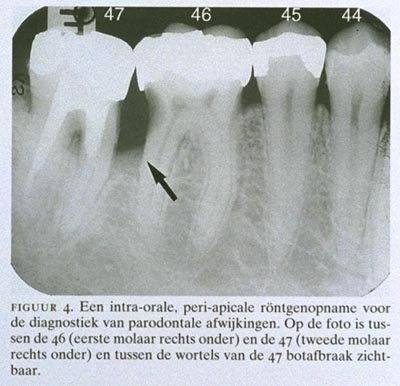

Bitewing-foto's worden ook gebruikt voor de diagnostiek van parodontale afwijkingen. Daarbij kan ook gebruik worden gemaakt van peri-apicale röntgenfoto's, waarop de elementen geheel worden afgebeeld. De aanwezigheid, de aard en de uitgebreidheid van aantastingen van het benige deel van het parodontium (steunweefsel) kunnen op röntgenfoto's worden beoordeeld (figuur 4).